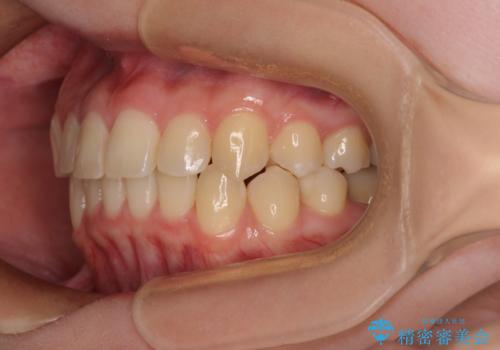

前歯のクロスバイト ギラギラのワイヤー装置で矯正治療

- 前歯のクロスバイトを改善したいとのことで来院された患者様です。

マウスピース矯正では前歯の神経への負担が大きいことを懸念され、ワイヤー装置による矯正治療を行うこととしました。

クロスバイトが改善する際は、前歯しか接触しないため、痛みがあったり食事が取りにくかったりと、不便な時期がありますが、1年強の短期間で無事に治療を終えることができました。